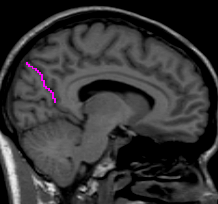

The insular cortex is “hidden” between the temporal and inferior parietal corticies. By drawing sulci lines in the sagittal view, we gain an outline of it in the coronal. Choose a sagittal slice where insula is clearly visible (Fig 1), then draw a “circle” around it (Fig 2). Do this for several slices and for both hemispheres.

Figure 1              Figure

2